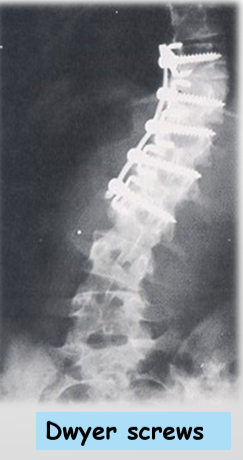

Treatment - Scoliosis

Observation: x-rays every 3 months

Bracing: curves that are flexible

Surgical: curves>40degrees, when underlying abnormality can be treated, attachment of corrective instruments (rods, screws, wires)